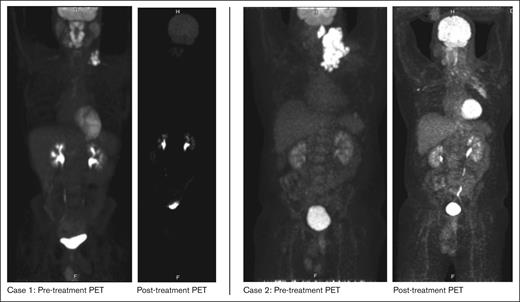

A male aged 23 years with asthma noticed left neck swelling which progressively worsened with associated fevers, chills, night sweats and weight loss. Computed tomography (CT) imaging of neck, chest, abdomen, and pelvis revealed disease localized to bilateral cervical lymph nodes (LN). Excisional biopsy of left cervical LN was notable for ALK+ LBCL with immunohistochemistry (IHC) stains showing positive ALK (cytoplasmic and golgi pattern), EMA, MUM1, weak CD45, weak CD79a, and CD138 (subset), with remaining stains shown in Table 1. Positron emission tomography-CT (PET/CT) revealed disease in palatine tonsil, adenoids, base of tongue, and left cervical and supraclavicular (SCV) LN. Bone marrow biopsy was negative for lymphoma involvement. He completed 3 cycles of CHOP (cyclophosphamide, doxorubicin, vincristine, and prednisone). Subsequent PET/CT revealed Deauville score of 4 in left cervical and SCV LN, thus the patient was started on crizotinib 250mg twice daily about 3 weeks after CHOP. He subsequently received localized radiation therapy to left cervical LN and a follow-up PET/CT after 3 months showed near CR. Surveillance CT scans every 6 months have shown ongoing CR while on crizotinib therapy. He has maintained a durable response to crizotinib for at least 6 years. His course has only otherwise been complicated by an incidental finding of a left subsegmental pulmonary embolism (PE), which was found on a surveillance scan in December 2019 and was managed with 3 months of rivaroxaban.

In summary, we report the first case series of adult patients with ALK+ LBCL who were treated with ALK inhibitors and attained meaningful and durable clinical responses. Both our patients had diseases that were resistant to standard-of-care treatment with CHOP. Initiation of an ALK inhibitor led to a rapid clinical response in both patients as demonstrated in Figure 1. Our first patient from case 1 has done exceptionally well with crizotinib as demonstrated by ongoing CR for >6 years without any dose-limiting toxicities. In contrast, our second patient, after an initial response, had PD after 3 months of crizotinib therapy and, thus, was switched to a second-generation ALK inhibitor, alectinib. He tolerated this well with response lasting 6 months and now in a CR while being treated with lorlatinib currently again in a CR after progressing while on alectinib.